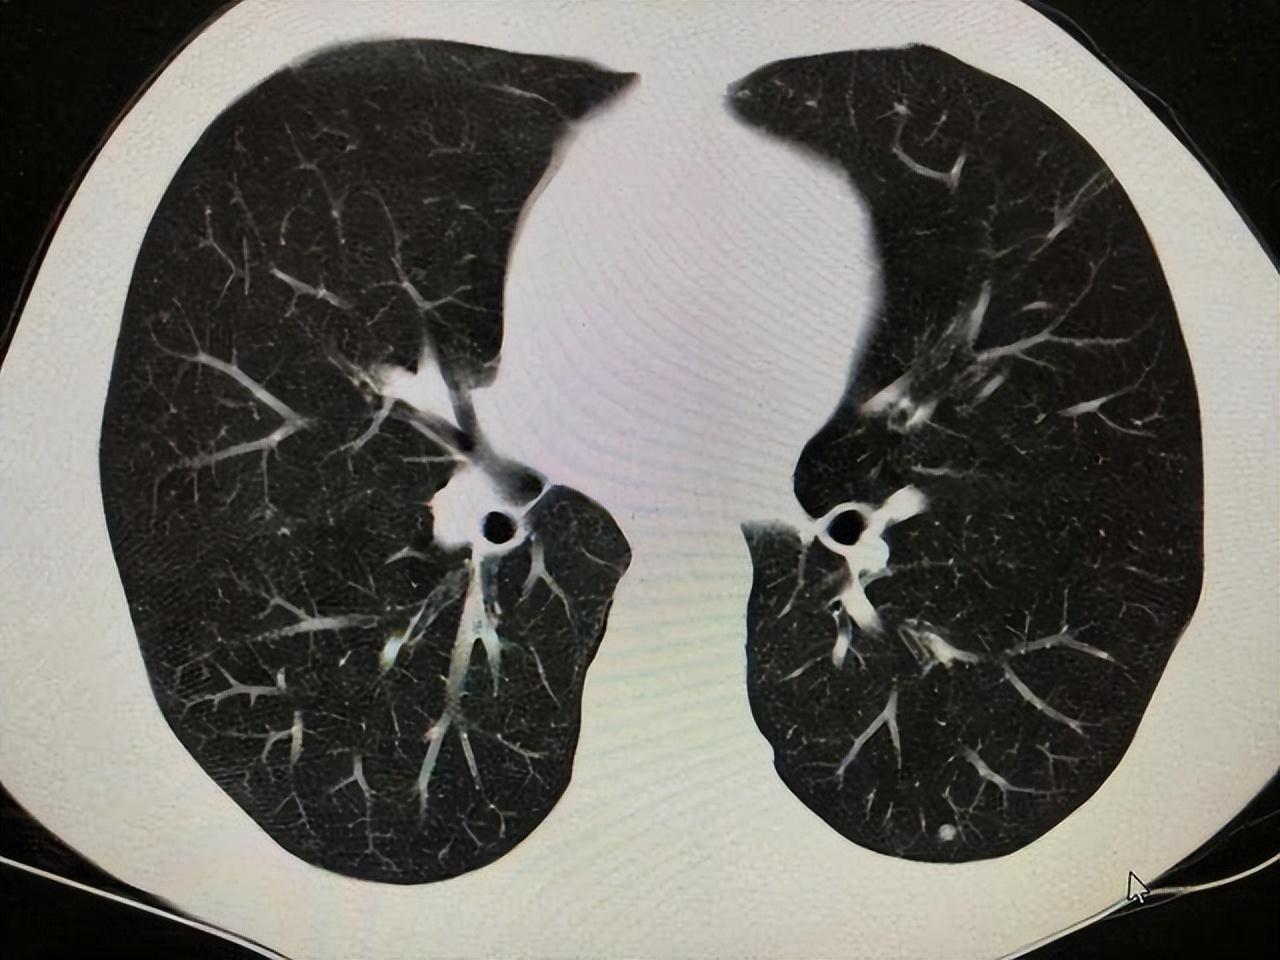

肺結(jié)節(jié)是指肺部出現(xiàn)的小圓形或橢圓形的異常結(jié)構(gòu),通常是通過(guò)CT等影像學(xué)檢查發(fā)現(xiàn)的,肺結(jié)節(jié)可能是良性的,也可能是惡性的,可能是感染引起的,也可能是其他原因?qū)е碌模l(fā)現(xiàn)肺結(jié)節(jié)并不一定意味著患有嚴(yán)重疾病。